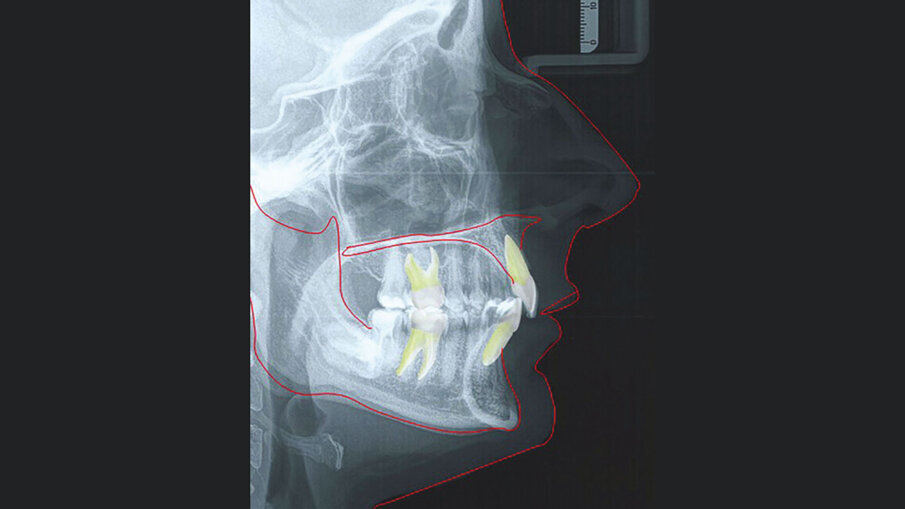

La paziente M. P. di anni 42 giunge alla nostra osservazione con la richiesta di un trattamento ortodontico di tipo estetico, al fine di migliorare l’allineamento dentale e l’esposizione del sorriso. All’analisi del volto si evidenzia un viso di forma quadrata, simmetrico ed un profilo dritto. All’esame funzionale non si rilevano disfunzioni dell’ATM. L’analisi cefalometrica (Figg. 3a-3c) evidenza una seconda classe scheletrica associata a ipodivergenza. Gli incisivi superiori presentano un’inclinazione rispetto al piano bispinale di 99,57° e la loro posizione rispetto alla linea A-Pg risulta nella norma. Gli incisivi inferiori (106,57°) sono protrusi rispetto al piano mandibolare e la loro posizione rispetto alla linea A-Pg risulta nella norma.

Figg. 3a-3c_Acquisizione dei records radiografici. Tracciato cefalometrico iniziale.

Figg. 3a-3c_Acquisizione dei records radiografici. Tracciato cefalometrico iniziale.

Figg. 3a-3c_Acquisizione dei records radiografici. Tracciato cefalometrico iniziale.